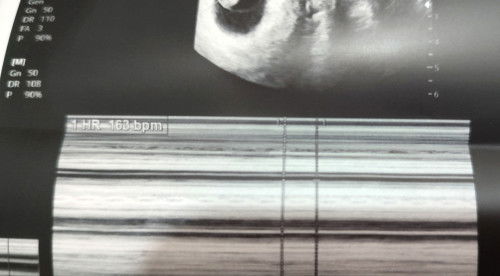

Is the 163bmp heart rate normal??

Mga mii normal po ba heart rate ni baby 163bmp, which is the normal heart rate is 110-160bmp. I'm currently 9weeks and 2days. #adviceplease #sharing #1sttimemom #newmom #pregnant #firsttimemom #help1sttimemompls

Ako mii 9 weeks 179bpm. Mabilis daw pero sabi ni ob, normal lang daw since di pa fully developed ang brain. Mukhang okay naman si baby, malikot sya sa ultrasound

Same tayo 163 din ako nung 8weeks ko. For our reference. 😊